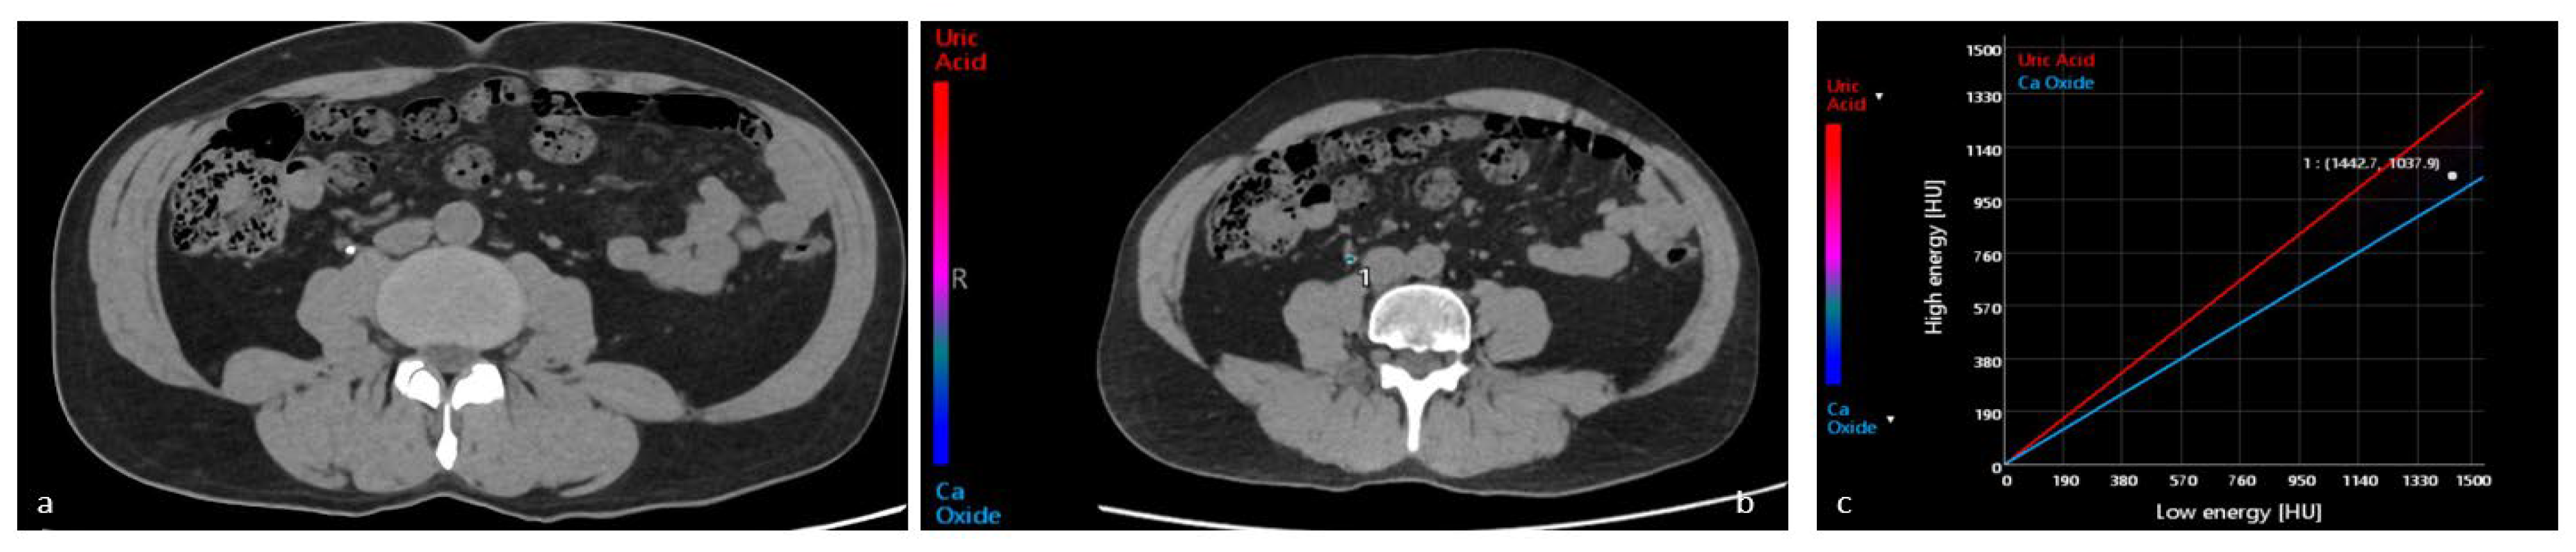

4.1. Characterization of Urinary Stones

- Spek, A.; Strittmatter, F.; Graser, A.; Kufer, P.; Stief, C.; Staehler, M. Dual Energy Can Accurately Differentiate Uric Acid-Containing Urinary Calculi from Calcium Stones. World J. Urol. 2016, 34, 1297–1302. [Google Scholar] [CrossRef]

- Lombardo, F.; Bonatti, M.; Zamboni, G.A.; Avesani, G.; Oberhofer, N.; Bonelli, M.; Pycha, A.; Mucelli, R.P.; Bonatti, G. Uric Acid versus Non-Uric Acid Renal Stones: In Vivo Differentiation with Spectral CT. Clin. Radiol. 2017, 72, 490–496. [Google Scholar] [CrossRef]

- Bonatti, M.; Lombardo, F.; Zamboni, G.A.; Pernter, P.; Pycha, A.; Mucelli, R.P.; Bonatti, G. Renal Stones Composition in vivo Determination: Comparison between 100/Sn140 KV Dual-Energy CT and 120 KV Single-Energy CT. Urolithiasis 2017, 45, 255–261. [Google Scholar] [CrossRef]